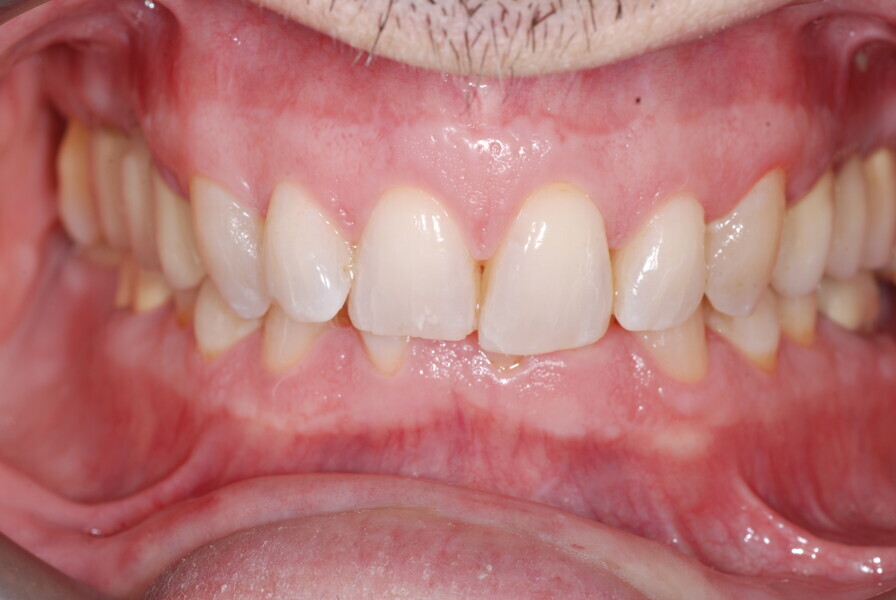

Le motif principal de consultation de ce patient âgé de 37 ans, était de rétablir l’alignement des dents antérieures sur les deux arcades. L’analyse faciale a indiqué une face courte avec un profil plat, mais une projection normale du menton (Figs. 9–12), et l’examen clinique a révélé une classe squelettique de type I (angle ANB = 0,89°) et une malocclusion de classe I avec supraclusion sévère (près de 100 %), une courbe de Spee très prononcée, un torque normal de l’incisive centrale supérieure (Ui-FH = 110°), un encombrement dentaire léger sur l’arcade maxillaire et modéré sur l’arcade mandibulaire (Figs. 13–18). Chez ce patient, les composantes de la supraclusion correspondaient à une dysmorphie squelettique grave correspondant à une hypodivergence (FMA = 14,24°), avec une inclinaison normale des incisives supérieures et inférieures et un angle goniaque réduit (110,46°). L’analyse du cliché céphalométrique indiquait une hauteur réduite de l’étage inférieur de la face associée à l’hypodivergence (Fig. 19). La seule option de traitement envisagée était un traitement orthodontique par aligneurs avec tous les éléments auxiliaires décrits (rampes d’occlusion, zones de pression, nivellement de la courbe de Spee dans les trois dimensions, élastiques de classe II et puissants contacts occlusaux) afin de corriger la supraclusion.

Le plan de traitement numérique (ClinCheck) avait prévu douze aligneurs pour l’arcade maxillaire et dix-sept pour l’arcade mandibulaire. Les objectifs du traitement visaient à combiner les mouvements verticaux d’extrusion des dents postérieures et les mouvements d’intrusion des dents antérieurs, au moyen de rampes d’occlusion, tout en utilisant des taquets d’extrusion pour assurer la désocclusion des dents postérieures et l’intrusion des dents antérieures inférieures, nécessaires au nivellement de l’arcade mandibulaire. La courbe de Spee a été nivelée et le profil plat ainsi que la position des lèvres ont été améliorés par une vestibulo-version des incisives supérieures et inférieures. Le plan avait prévu des élastiques de classe II pour faciliter la vestibulo-version des dents inférieures et les puissants contacts occlusaux postérieurs, avec une extrusion relative des dents postérieures. Une morphologie plus large de l’arcade et une intercuspidation idéale ont été obtenues par des mouvements de torque proches de 0° des dents latérales et postérieures supérieures. Aucune conception technique excessive n’avait été prévue dans le plan de traitement numérique. En raison de l’âge du patient, les aligneurs ont été changés tous les dix jours, dans le cadre d’un traitement d’une durée inférieure à six mois. À la fin de la première série d’aligneurs (Figs. 20–24), un nouveau plan de traitement numérique comportant cinq autres aligneurs a été conçu, en vue d’améliorer l’intercuspidation des molaires sans élastiques. La durée totale du traitement a donc été prolongée jusqu’à 7,5 mois puisque les aligneurs supplémentaires étaient changés toutes les semaines.

À la fin du traitement, on pouvait observer une relation de classe I des canines et des molaires, une légère augmentation de l’inclinaison des incisives supérieures (Ui-FH = 112°), une correction complète de l’inclinaison des incisives inférieures (IMPA = 97,09°) grâce à la vestibulo-version, et une légère amélioration de l’hypodivergence (SN-GoGn = 27°) résultant de l’extrusion relative des dents postérieures, et de l’utilisation d’élastiques de classe II — petite variation (1°) très intéressante compte tenu de l’âge du patient (Figs. 25–35). La ligne du sourire était harmonieuse et correspondait à une relation idéale entre les incisives supérieures et la lèvre inférieure. Le sourire avait été élargi grâce au contrôle du torque des segments latéraux et postérieurs.